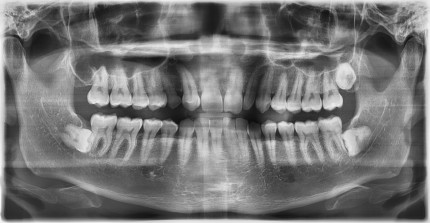

쿨쿨플란트치과 고난이도 사랑니발치 케이스

쿨쿨플란트치과 사랑니, 매복치발치 치료 전후사진